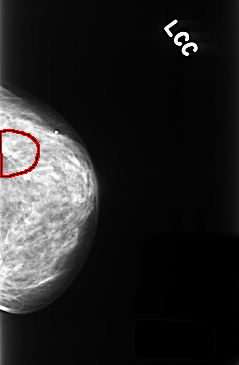

ics_version 1.0 filename C-0396-1 DATE_OF_STUDY 29 11 1996 PATIENT_AGE 68 FILM FILM_TYPE REGULAR DENSITY 3 DATE_DIGITIZED 13 10 1998 DIGITIZER LUMISYS LASER SEQUENCE LEFT_CC LINES 4376 PIXELS_PER_LINE 2864 BITS_PER_PIXEL 12 RESOLUTION 50 OVERLAY LEFT_MLO LINES 4376 PIXELS_PER_LINE 2808 BITS_PER_PIXEL 12 RESOLUTION 50 OVERLAY RIGHT_CC LINES 4392 PIXELS_PER_LINE 2760 BITS_PER_PIXEL 12 RESOLUTION 50 NON_OVERLAY RIGHT_MLO LINES 4392 PIXELS_PER_LINE 2808 BITS_PER_PIXEL 12 RESOLUTION 50 NON_OVERLAY |

FILE: C_0396_1.LEFT_CC.OVERLAY TOTAL_ABNORMALITIES 1 ABNORMALITY 1 LESION_TYPE MASS SHAPE OVAL MARGINS CIRCUMSCRIBED ASSESSMENT 3 SUBTLETY 4 PATHOLOGY BENIGN TOTAL_OUTLINES 1 BOUNDARY |